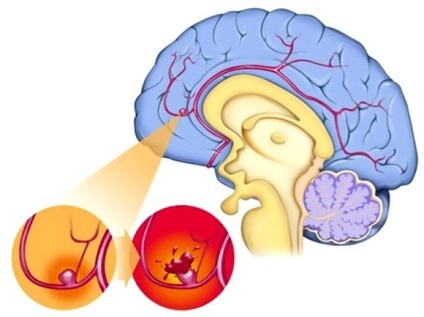

Uneori mentionat ca subarahnoidiană accident vascular cerebral hemoragie hemoragic. Acest lucru se datorează faptului că ambele tipuri de accident vascular cerebral cauzat de sângerare. Acestea diferă numai pe localizarea hemoragiei. Accident vascular cerebral hemoragic adesea situate direct în zona creierului, accident vascular cerebral și subarahnoidiană - în spațiul subarahnoidian.

hemoragie subarahnoidiană

Există următorii factori care pot duce la hemoragii în spațiul subarahnoidian:

- stil de viață nesănătoase;

- anemia celulelor secera;

- hipertensiune (tensiune arterială ridicată);

- tulburări de coagulare a sângelui;

- deteriorări mecanice;

- acceptarea unor medicamente (anticoagulante);

- alte tipuri de accidente vasculare cerebrale.

Ruperea unui anevrism arterial - este de 80%, astfel încât acest lucru este considerat un factor major în lista cauzelor de hemoragie subarahnoidiană. De la 10 până la 60% din toate cazurile de hemoragiilor post-traumatice, de asemenea, să apară în acest tip de leziuni cerebrale. Frecvența lor cu vârsta este mai mare, precum și utilizarea sporită a alcoolului subtiaza vasele de sange, crescand riscul de acest tip de accident vascular cerebral, după o accidentare.